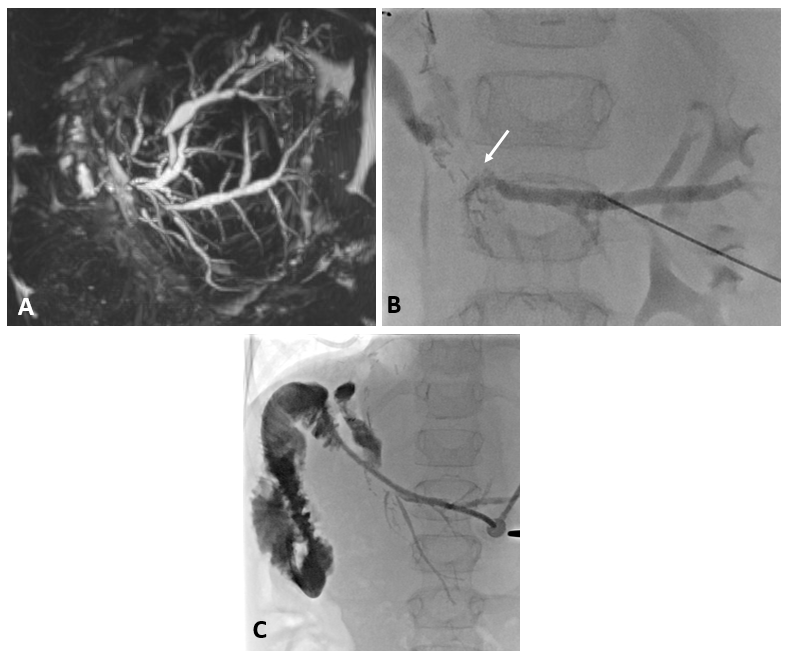

8 jähriger Junge nach Transplantation der linksseitigen Lebersegmente

In der Bildgebung (MRCP-Bild, A) zeigt sich eine Erweiterung der Gallenwege in der Leber, bedingt durch eine Engstelle an der Verbindung der Gallenwege (Gallenwegsanastomose). Entlastung der gestauten Gallenwege mittels PTCD. Punktion eines in der Leber gelegenen Gallenweges mit Hilfe von Ultraschall. Gabe von Kontrastmittel über die Punktionsnadel (B). Darstellung des gestauten Gangsystems und der Engstelle (Pfeil). Anschließende Anlage einer Ableitung (Drainage) zur Entlastung des Gallenwegssystems (C).

Abb 1

A